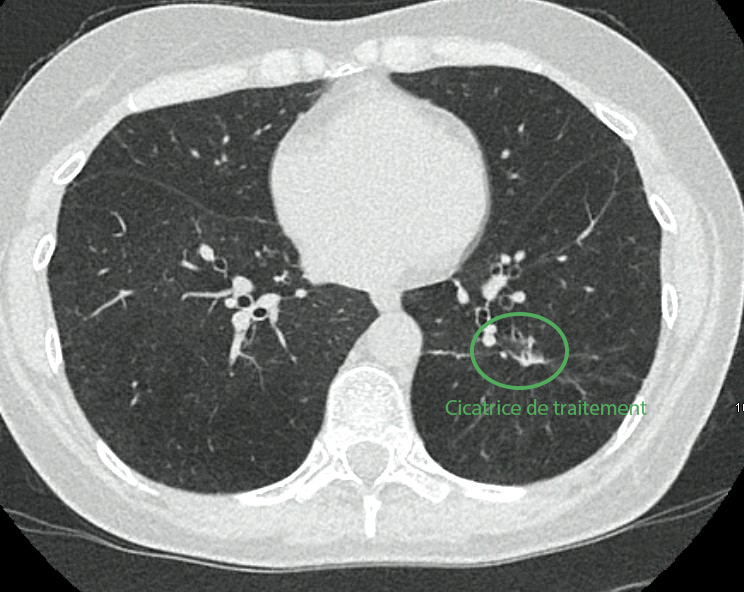

Traitement pulmonaire par cryoablation

La lésion pulmonaire est traitée par cryothérapie, permettant une destruction efficace tout en évitant une chirurgie lourde (lobectomie).

Un pneumothorax, complication attendue, est pris en charge simplement avec un drain temporaire.

Résultat

Le contrôle à distance montre une réponse complète des lésions, sans nouvelle métastase, permettant la poursuite d’une simple surveillance.

En images

Images du traitement des organes (poumon et foie) avant, pendant et après le traitement.